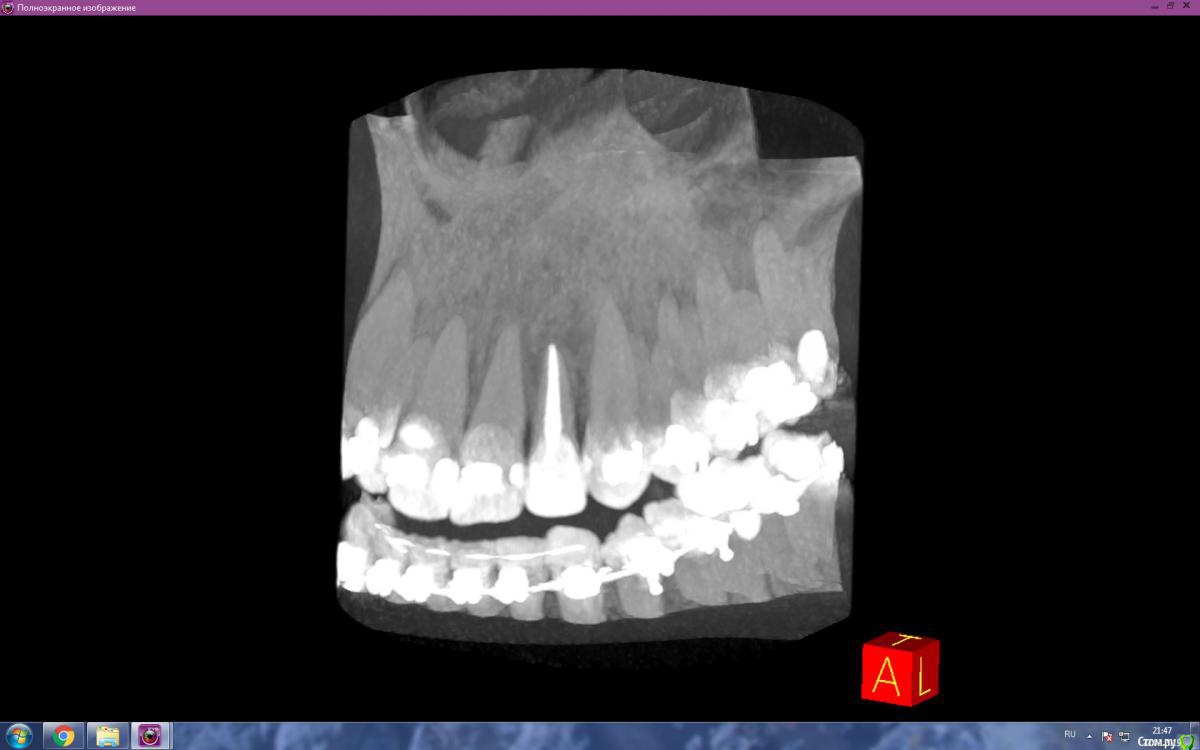

Zubik_Zubik Опубликовано 1 марта, 2019 Автор Поделиться Опубликовано 1 марта, 2019 (изменено) Как смог нарезал в кт. 1.Ортопед сказал что с небной подрезать нужно чутка.2.Насколько разумен такой вариант пока установлены брекеты. Спелить пломбу переклеить брекет с целью экструзии зуба, потом снова пломба и ретейнер. После небольшого отдыха нормальная коронка +3 винира 21, 11, 12. Спасибо Изменено 1 марта, 2019 пользователем Zubik_Zubik Ссылка на комментарий